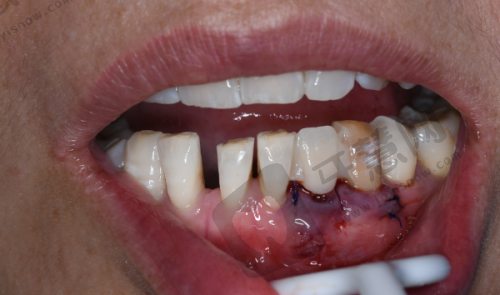

实例2:30岁李女士,前牙缺损选即刻种植,18000元当天告别“豁牙”

李女士因骑车摔倒撞断上前牙,牙根残留无法保留。拜博口腔张医生检查发现牙槽骨条件良好,推荐即刻种植 + 临时牙冠修复。手术采用瑞士士卓曼亲水种植体,拔除残根后即刻植入植体,当天戴上临时牙冠,避免缺牙尴尬。6个月后更换恒久全瓷冠,色泽与邻牙一致,同事均未察觉是种植牙。李女士特别满意:“重要会议前种牙,完全没影响工作形象。”